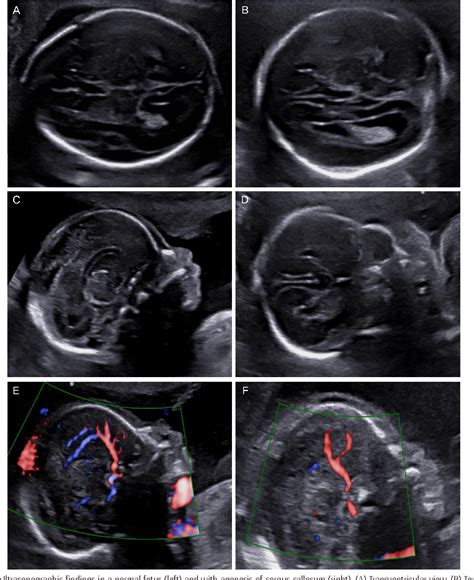

Corpus Callosum Agenesis is a congenital condition, meaning it is present at birth. It can occur as an isolated condition or as part of a broader syndrome. The severity of symptoms can vary widely among individuals, ranging from mild to severe. The condition is often diagnosed through imaging techniques such as magnetic resonance imaging (MRI), which can clearly visualize the absence or underdevelopment of the corpus callosum.

Diagnosis typically involves a combination of clinical evaluation and imaging studies. MRI is the gold standard for diagnosing Corpus Callosum Agenesis, as it provides detailed images of the brain’s structure. Additional tests, such as electroencephalography (EEG) for seizure monitoring and genetic testing, may also be conducted to identify underlying causes and associated conditions.

• Neuroimaging Techniques: Developing advanced imaging techniques to better visualize and understand brain structure and function in individuals with Corpus Callosum Agenesis.